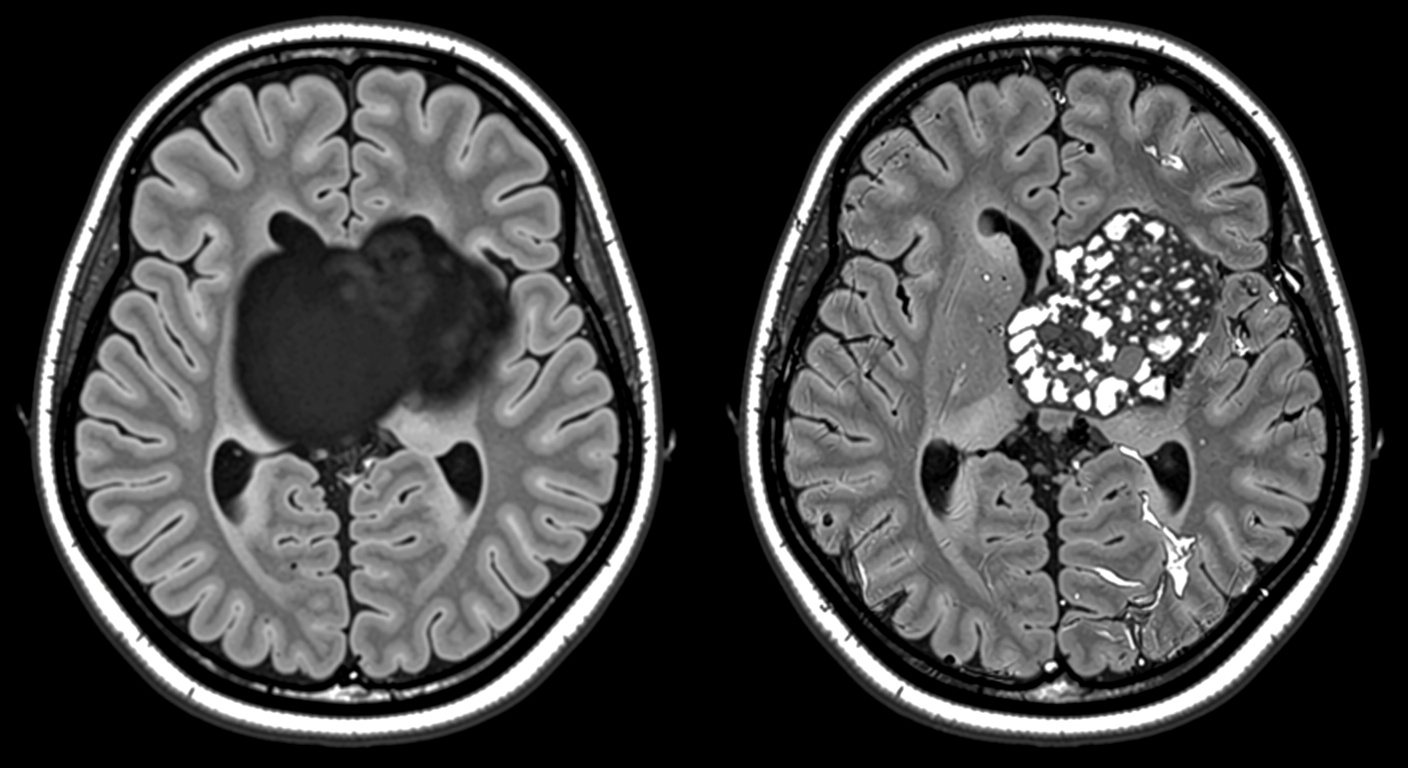

Parmi ces causes non traditionnelles, les scientifiques ont identifié la « dissection spontanée de l’artère coronaire », ou DSAC. Il ne s’agit pas d’un bouchon, mais d’une déchirure de la paroi de l’artère. Le sang s’accumule alors entre les couches de la paroi, ce qui réduit ou interrompt le flux sanguin vers le muscle cardiaque. Les auteurs de l’étude ont calculé que ce phénomène est six fois plus fréquent chez les femmes que chez les hommes. Bien que les facteurs de risque soient encore mal cernés, des éléments comme la grossesse, un stress émotionnel ou physique, ainsi que des défauts du tissu musculaire des vaisseaux semblent favoriser cette pathologie.